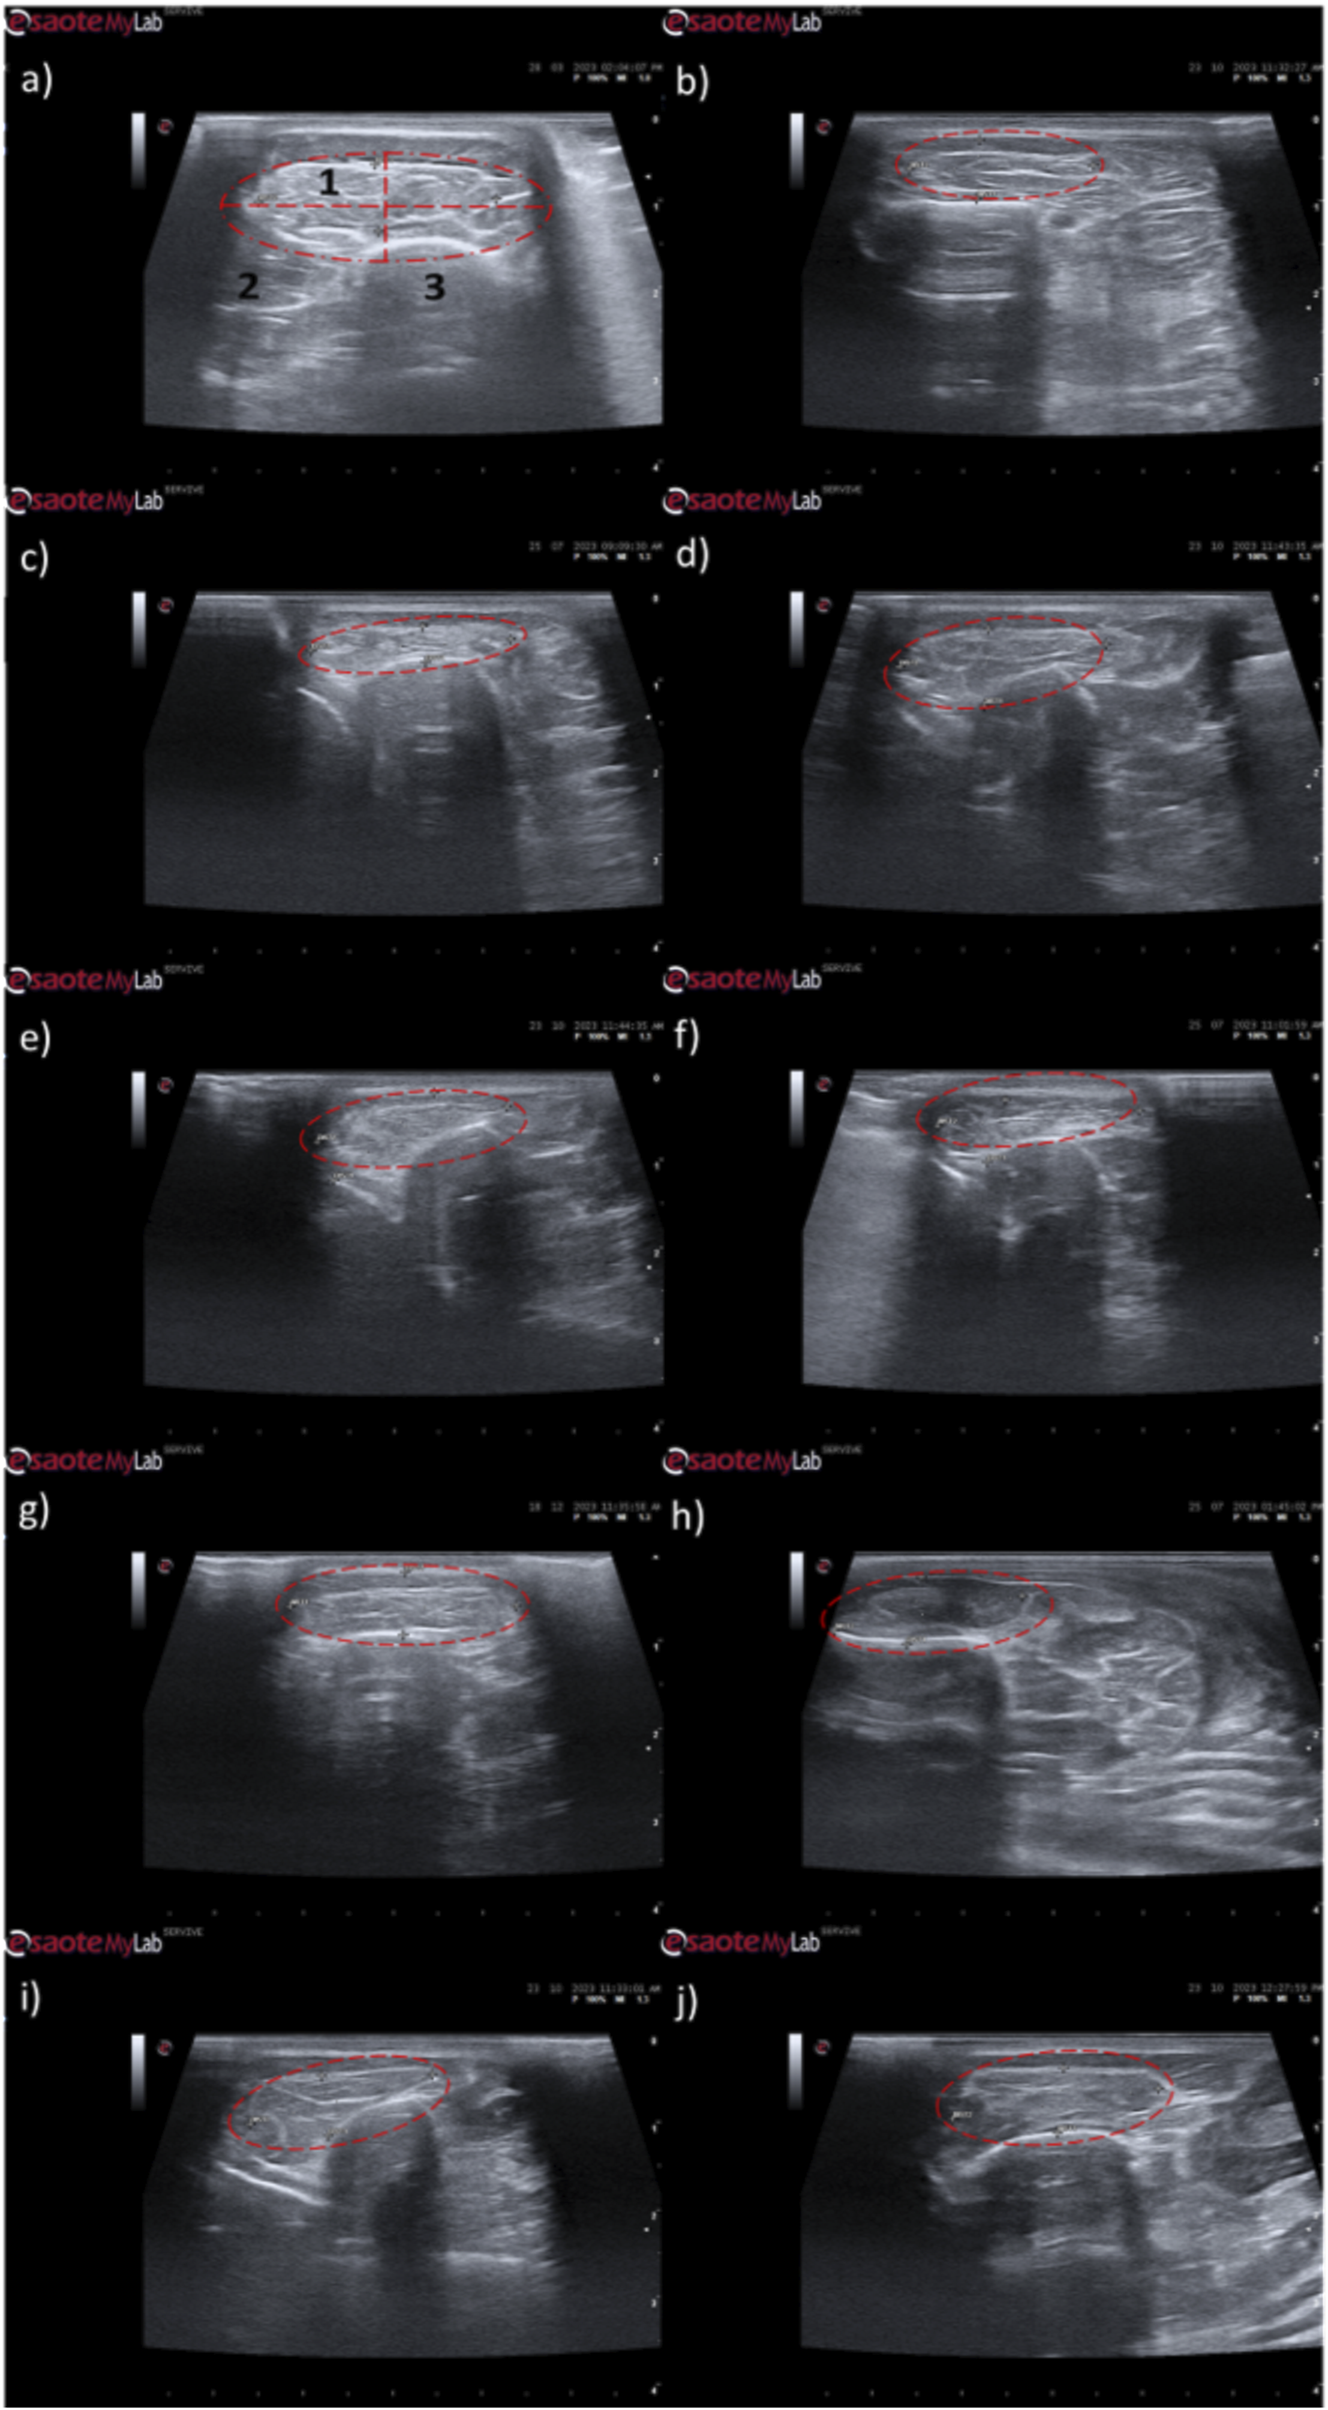

The results of the ultrasound evaluation of the cranial tibial muscles can be seen in Figure 9 and Figure 10, for the ultrasound images obtained and for the results of muscle measurements, respectively. The complete values of muscle width and thickness measured using ultrasound can be found in Supplementary Table S12, and the statistical differences observed in T24 in Supplementary Table S13.

FIGURE 9

Ultrasonographic appearance of the cranial tibial muscle as an effector muscle of the injured common peroneal nerves subject to different treatments: (a) intact common peroneal nerve (UC); (b–d) nerves that received an EtE suture 1 month, 3 months and 6 months after injury, respectively; (e–g) nerves that received a NGC 1 month, 3 months and 6 months respectively; (h–j) nerves that received the combination NGC-CM 1 month, 3 months and 6 months after injury, respectively. The red dashed circle delimits the muscle, in which the thickness (vertical red dashed line) and width (horizontal red dashed line) were measured. 1- Cranial tibial muscle; 2- long digital extensor muscle; 3- tibia.

Ultrasonographically, significant variations were observed in all study groups over time compared to the UC group, where the muscles presented the expected ultrasound appearance for this muscle, with homogeneous echogenicity and a well-defined fibrillar pattern. After 1 month, due to acute denervation phenomena, hypoechogenicity is observed in all muscles secondary to the expected acute edema and inflammatory infiltration, reflecting the absence of the muscle’s contractile capacity. This ultrasound pattern partially masks the typical fibrillar pattern of the cranial tibial muscles, being particularly evident in the NGC-CM group followed by EtE. At 3 months, the hypoechogenic ultrasound appearance is replaced by a hyperechogenic pattern due to the phenomena of infiltration of fibrous tissue, fat and loss of intracellular fluid. The fibrillar pattern is observed, although in a disorganized way. This phase translates the phenomena of muscle degeneration and repair. The most evident disorganization is observed in the EtE and NGC groups. At 6 months, the muscles present an ultrasound pattern closer to healthy muscle, although still slightly hypoechoic, revealing a reversal of the fibrous, adipose and inflammatory infiltration phenomena. The fibrillar pattern is again easily identifiable, although still disorganized. The NGC and NGC-CM groups present a more organized ultrasound appearance than the EtE group.

One month after the injury, a decrease in muscle width and thickness was observed in all groups. The exception is made in the NGC group, which maintained its thickness stable throughout the 6 months of study. At 3 months, the EtE group had already started to recover its thikness and maintained a stable width. The NGC-CM group presented a lower width and thickness than those measured at 1 month. The NGC group slightly increased width. At 6 months the EtE and NGC-CM groups showed an evident increase in thickness, as well as in width. The NGC group also evidently increased its width. In general, the EtE group had the greatest muscle atrophy 1 month after the injury, but showed good levels of recovery at 6 months (7.60 ± 0.58 mm for thickness and 18.74 ± 3.75 mm for width). The NGC-CM group also had a drop in thickness and width values, with the lowest final values for both parameters at 6 months (6.70 ± 0.42 mm for thickness and 17.27 ± 4.05 mm for width). The NGC group maintained stable thickness values and very close to the control value over the 6 months (7.60 ± 0.65 mm), and in terms of width, although it followed a pattern of evolution identical to the other groups, it also presented the highest value (18.07 ± 0.29 mm) among the therapeutic groups. No statistical differences were observed between the therapeutic groups or between them and the UC group in any parameter or timepoint.